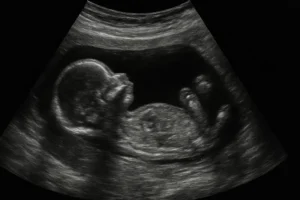

• Ultrahang (11–14. hét): tarkóredő, orrcsont, érzékenység 70–75%.

• Kombinált teszt (11–14. hét): ultrahang + anyai vér, érzékenység 80–85%.

• NIPT (10. hét-től): anyai vérben keringő magzati DNS, érzékenység 99%, nem invazív.

• Invazív diagnosztika (CVS, amniocentesis): 100%-os érzékenység, vetélési kockázattal.

Az ultrahang, kombinált teszt és NIPT szűrővizsgálatok, nem diagnosztikusak. Pozitív eredmény esetén invazív vizsgálat szükséges. A választott módszer függ az anyai életkortól, kockázati tényezőktől és személyes preferenciáktól.